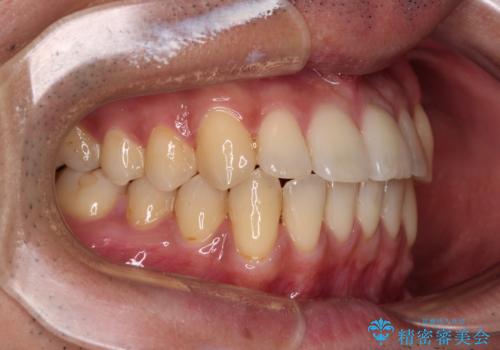

ワイヤー装置での上下前歯の部分矯正

部分矯正は咬み合わせが不安定になったり、スペースができてしまったりと、適用となる患者様は極めて限られますが、こちらの方はスムーズに治療を終えることができました。